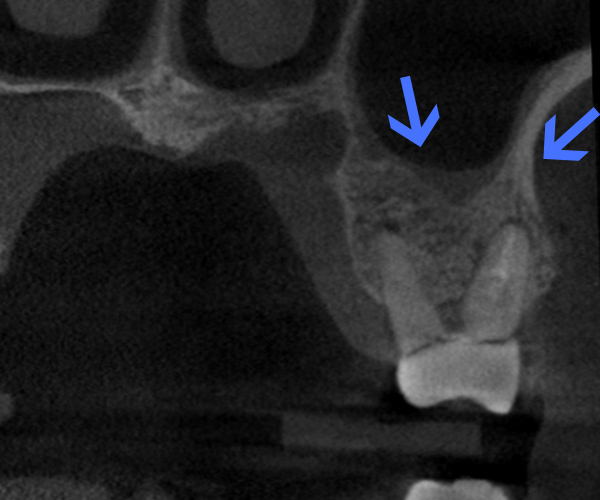

Before

歯性上顎洞炎(副鼻腔炎)

根尖病巣により洞底膜がラッパ状に開いている。